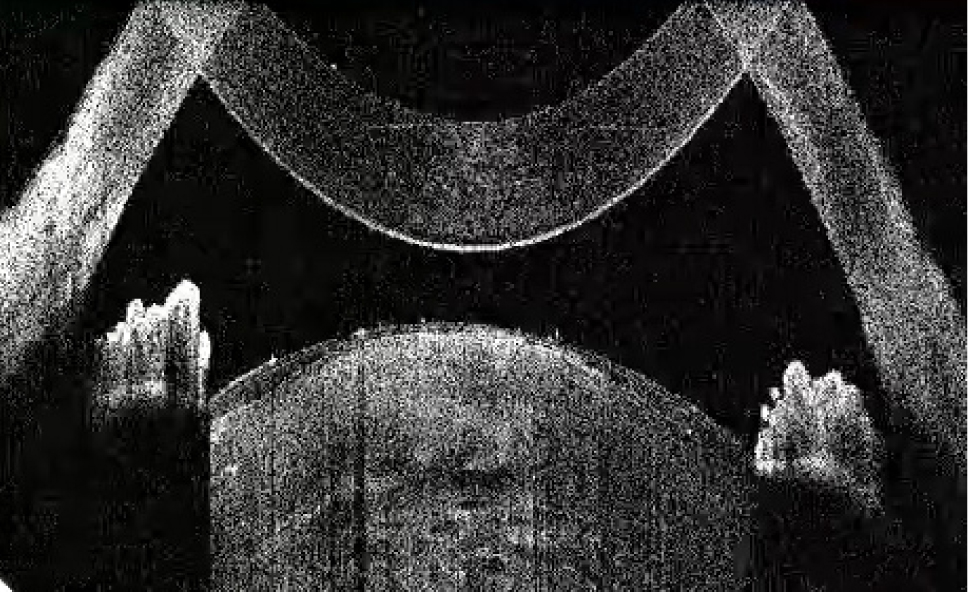

Рис. 1. Тип 1 перезрелой катаракты: равномерно расположенные кортикальные волокна, минимальные внутрихрусталиковые щели, отсутствие оводнения кортикальных масс

Рис. 4. Тип 4 перезрелой катаракты: гомогенные передние кортикальные слои хрусталика вида «матового стекла»